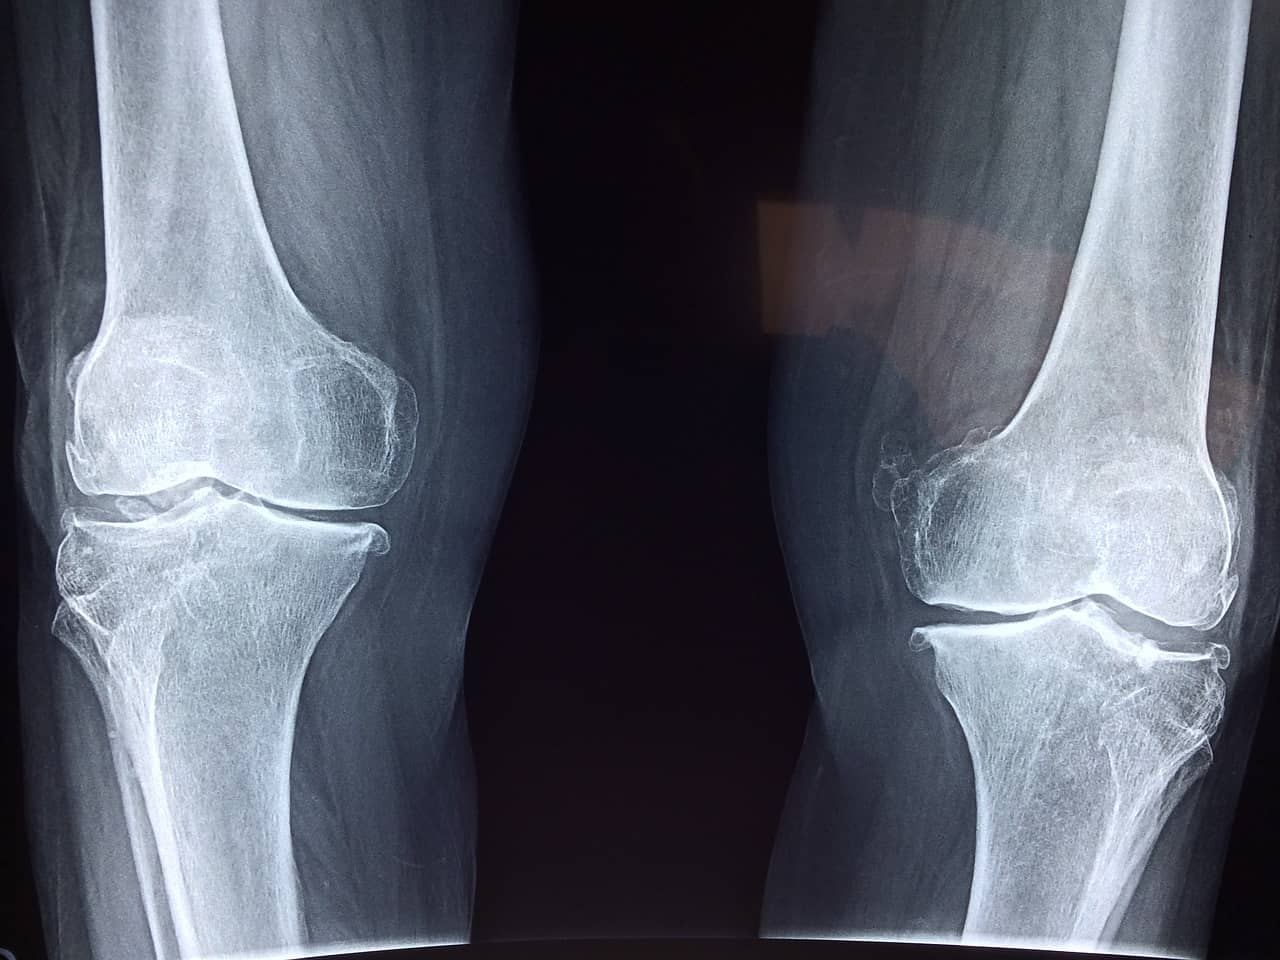

퇴행성 관절염은 관절을 구성하는 연골이 노화 또는 과도한 사용으로 인해 점진적으로 닳아 없어지면서 발생하는 질환입니다. 주로 무릎, 고관절, 척추와 같은 하중이 많이 가해지는 관절에 발생하며, 50대 이상에서 흔히 나타납니다.

이 질환의 대표적인 증상으로는 관절 부위의 통증, 부종, 뻣뻣함, 관절운동의 제한이 있습니다. 초기에는 증상이 경미하지만, 시간이 지날수록 통증이 심해지고 일상생활에 영향을 미칠 수 있습니다.

퇴행성 관절염의 치료는 크게 보존적 치료와 수술적 치료로 나뉩니다. 보존적 치료에는 약물치료, 물리치료, 체중 관리, 그리고 관절운동 강화 운동이 포함됩니다. 특히 항염증제(NSAIDs)는 통증과 염증 완화에 효과적입니다. 물리치료는 관절 주변의 근육을 강화해 관절 부담을 줄이는 데 도움을 줍니다. 체중 관리 역시 관절에 가해지는 부담을 줄이는 중요한 방법입니다.

증상이 심하거나 보존적 치료로 개선되지 않는 경우 수술적 치료가 필요할 수 있습니다. 인공관절 치환술은 심한 퇴행성 관절염 환자들에게 흔히 시행되는 수술로, 관절 기능 회복에 탁월한 효과를 보입니다.